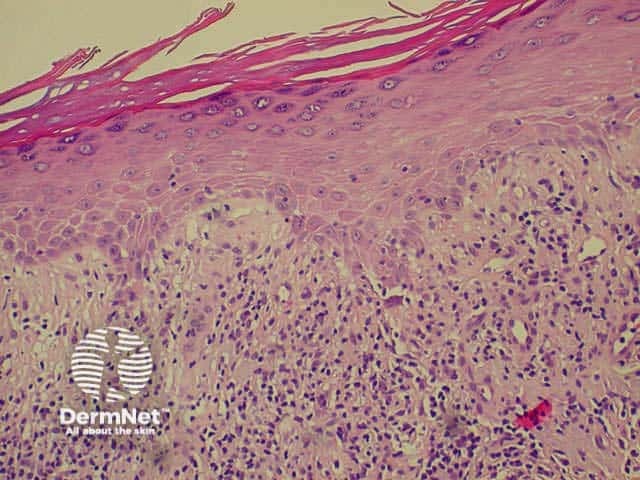

Lichenoid histology refers to liquefaction degeneration of basal layer, dermal infiltration of inflammatory cells hugging the basal layer, colloid bodies (degenerating keratinocytes) and dermal melanin.

Low power view Liquefaction degeneration